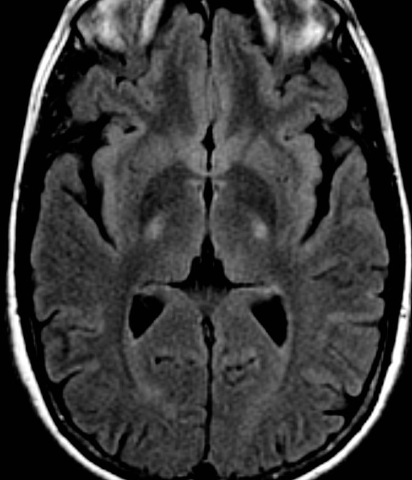

2. 루게릭병(ALS) 원인

루게릭병의 원인에 대해서는 여전히 수수께끼가 남아 있습니다. 광범위한 연구가 진행되었지만 루게릭병의 정확한 원인은 아직 밝혀지지 않았습니다.

유전적 요인이 루게릭병의 일부에 영향을 미치는 것으로 알려져 있으며, 특정 유전자 돌연변이가 가족성 루게릭병과 관련이 있는 것으로 알려져 있습니다.

그러나 대부분의 루게릭병은 명확한 유전적 연관성 없이 산발적으로 발생합니다. 독소 노출이나 바이러스 감염과 같은 환경적 요인도 잠재적인 원인으로 추정되고 있습니다.

그러나 유전적 소인과 환경적 영향 사이의 복잡한 상호 작용에 대해서는 아직 현재 더 조사와 연구가 진행 중이고, 더 연구가 필요한 영역입니다.